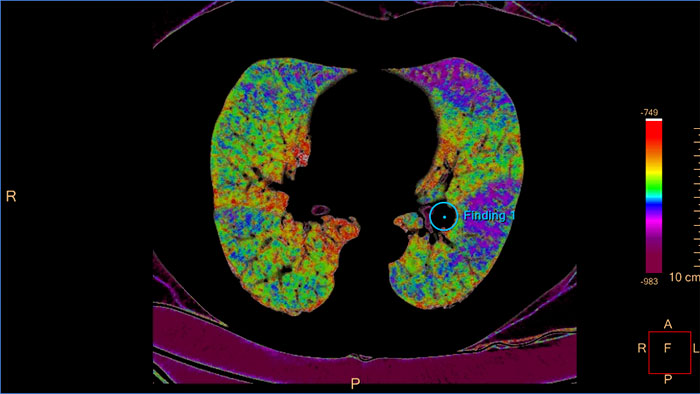

CT COPD to quantify diffuse lung disease

The clinical application helps visualize and quantify the destructive process of diffuse lung disease (e.g. emphysema), providing a guided workflow for airway analysis, reviewing and measuring airway lumen, and assessing air trapped.

- COPD

CT COPD

Quantify diffuse lung disease

CT COPD helps visualize and quantify the destructive process of diffuse lung disease (e.g. emphysema). The application provides a guided workflow for airway analysis, reviewing and measuring airway lumen, and assessing air trapped.

Benefits

- Automatic lung and lobes segmentation.

- Automatic airway extraction, airway tree segmentation and navigation path extraction, enabling the measurement of airway parameters such as lumen diameter and wall cross-section.

- Tools for qualitative and quantitative temporal comparison of up to four follow-up studies in order to determine the progression of the disease.